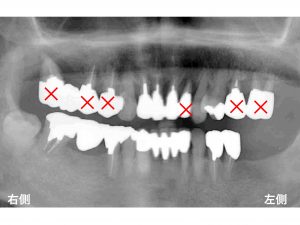

初診時のレントゲンです。

以下の赤丸がグラグラしている歯です。

以下の×印は、抜歯となります。